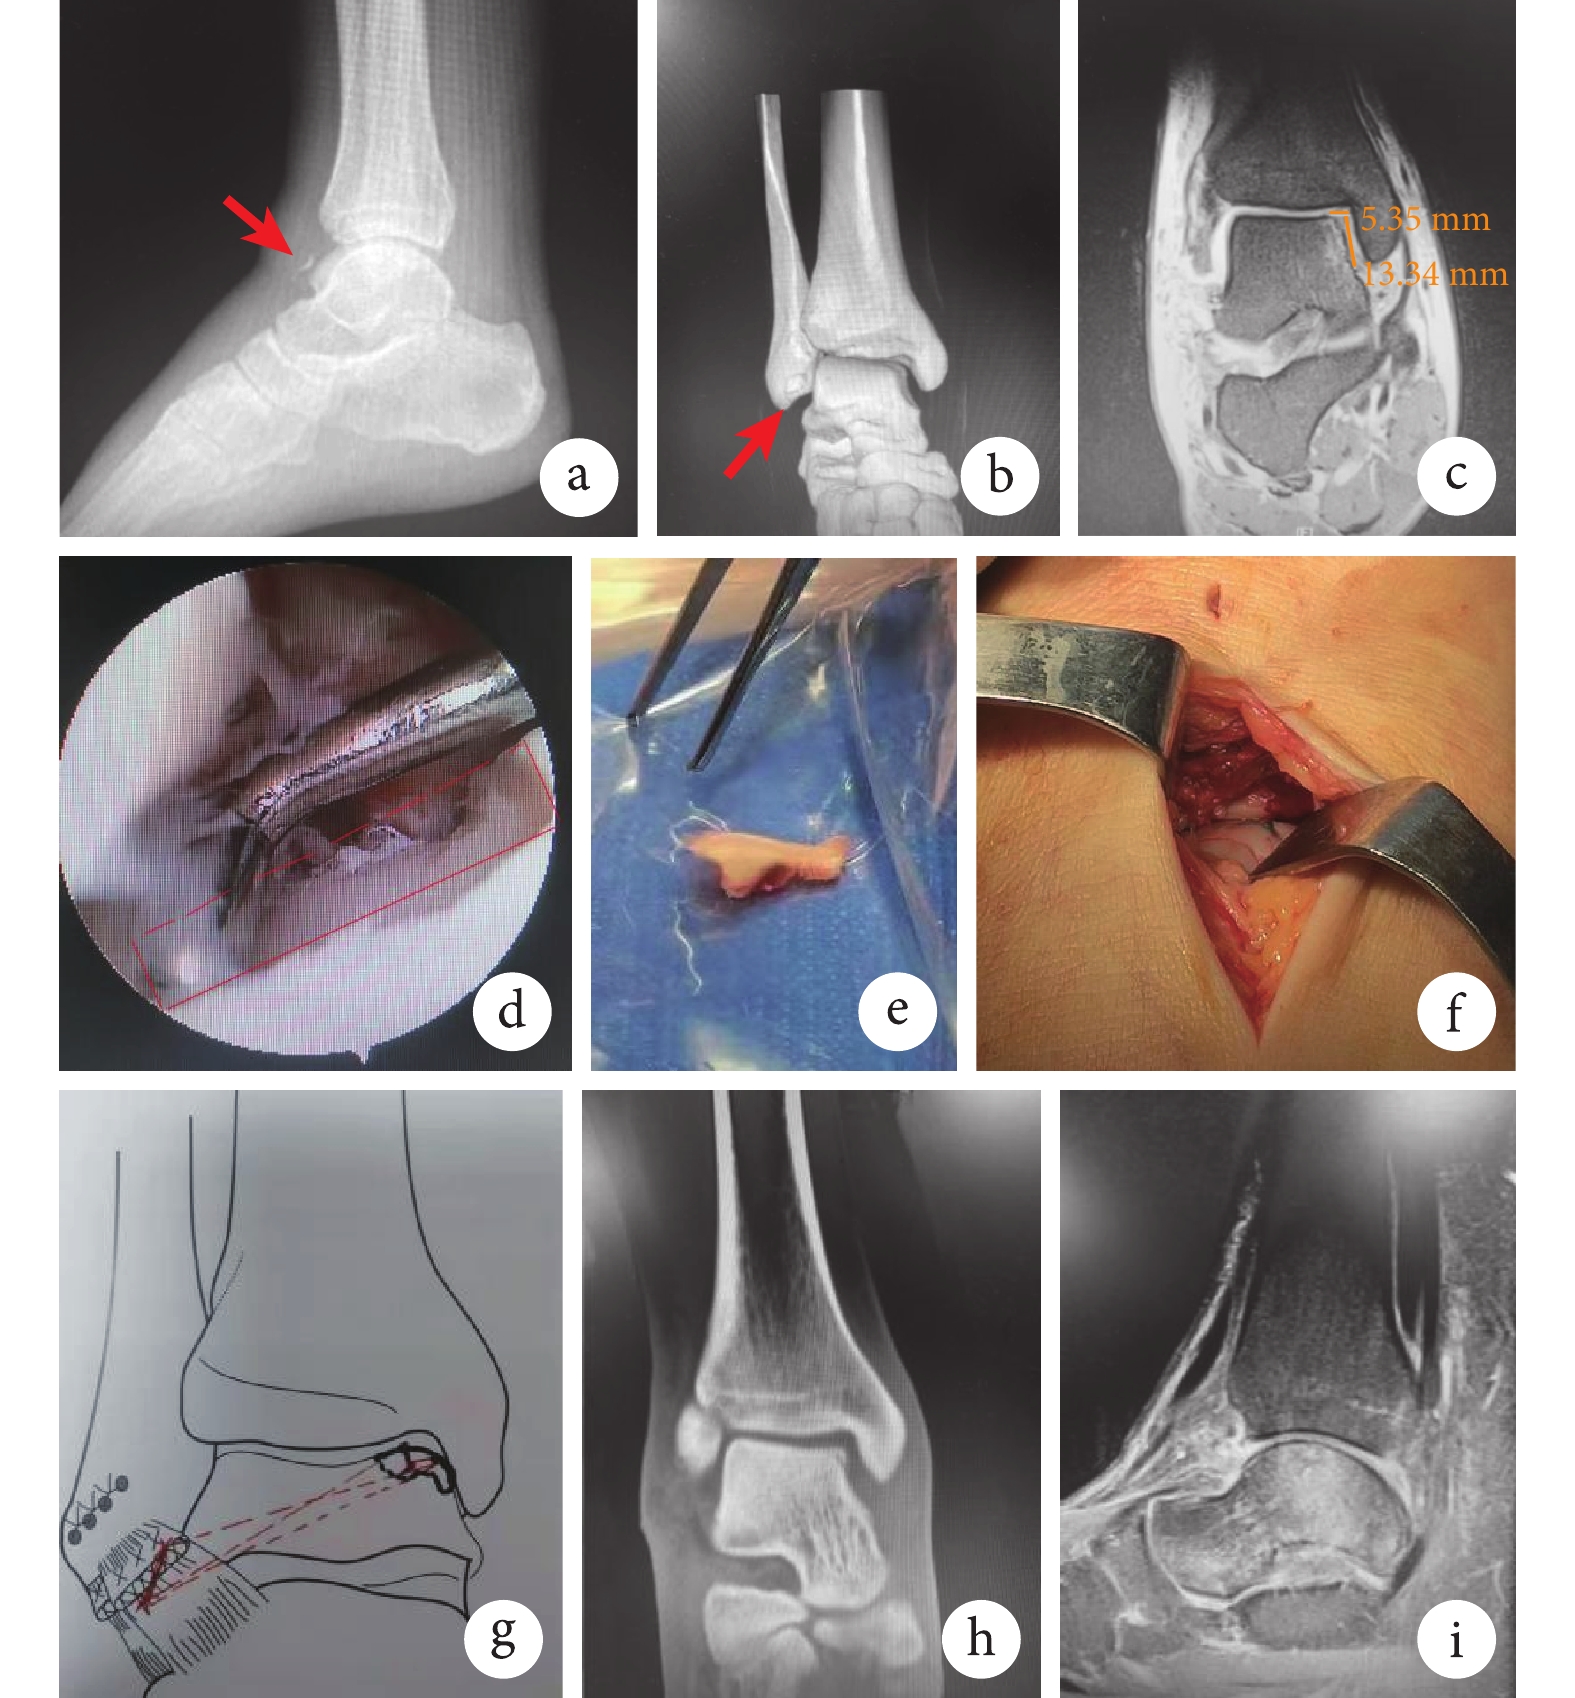

患者 男,24歲。因“扭傷致右踝關節腫脹疼痛、活動受限5 d”于2021年10月入院。查體:右踝關節腫脹、活動受限,距腓前韌帶止點壓痛(+),踝關節抽屜試驗(+)。疼痛視覺模擬評分(VAS)7分,美國矯形足踝協會(AOFAS)評分48分。X線片示右踝關節前方軟組織內小片狀高密度影;CT示右距骨前內緣骨折,小骨碎片游離;MRI示右距骨前內側骨折合并骨髓水腫,右踝距腓前韌帶完全斷裂(圖1a~c)。診斷為右距骨骨軟骨骨折合并距腓前韌帶斷裂。

采用三隧道懸吊固定法固定骨軟骨塊,錨釘修復外側距腓前韌帶。全身麻醉下,首先踝關節鏡下探查,建立踝關節內外側入路,鏡下見距骨內側穹窿部前內方骨軟骨骨折(圖1d),骨軟骨碎片游離至踝關節外側間隙,大小為1.7 cm×1.5 cm×0.5 cm,此時不取出。然后,作右外踝遠端弧形切口,長度約4 cm。分離各層組織,見距腓前韌帶完全斷裂,游離骨軟骨碎片位于距腓外側間隙,將其完整取出(圖1e)。再作右內踝前方切口,長度約5 cm。分離并暴露距骨內側骨軟骨骨折缺損處,解剖復位游離骨軟骨碎片后,用1.2 mm克氏針沿距骨內上方骨軟骨碎片表面至距骨外下方依次鉆3條隧道,呈“品”字結構。用半月板前角縫合器穿過其中1條隧道,引入2條不可吸收縫線,分別從另外兩隧道各引出1條縫線尾端至距骨外側端,2條縫線各自打結固定骨軟骨碎片(圖1f、g)。最后,于腓骨遠端距腓前韌帶止點處擰入2枚2.9 mm可吸收縫線錨釘,縫合距腓前韌帶,檢查踝關節抽屜試驗為陰性后關閉切口。

術后石膏固定踝關節于中立位,第5周改為佩戴支具8周,期間允許患者扶拐患肢部分負重下地行走。術后3個月患者恢復正常行走,右踝關節存在輕度疼痛,VAS評分為3分。術后6個月右踝關節無疼痛,VAS評分為1分;CT復查見右距骨內側骨軟骨碎片解剖復位(圖1h)。術后1年患者行走正常,右踝關節活動無受限,背伸20°、跖屈40°,恢復至傷前運動水平,AOFAS評分達94分;MRI復查示骨折端愈合,距骨軟骨面完整,距腓前韌帶愈合良好(圖1i)。

a~c. 術前X線片、CT及MRI 箭頭示骨折處;d. 術中踝關節鏡下見距骨內側穹窿部前內方骨軟骨骨折后缺損區;e. 術中取出游離距骨骨軟骨碎片;f、g. 術中不可吸收縫線三隧道懸吊固定法固定骨軟骨碎片及手術示意圖;h. 術后6個月CT;i. 術后1年MRI